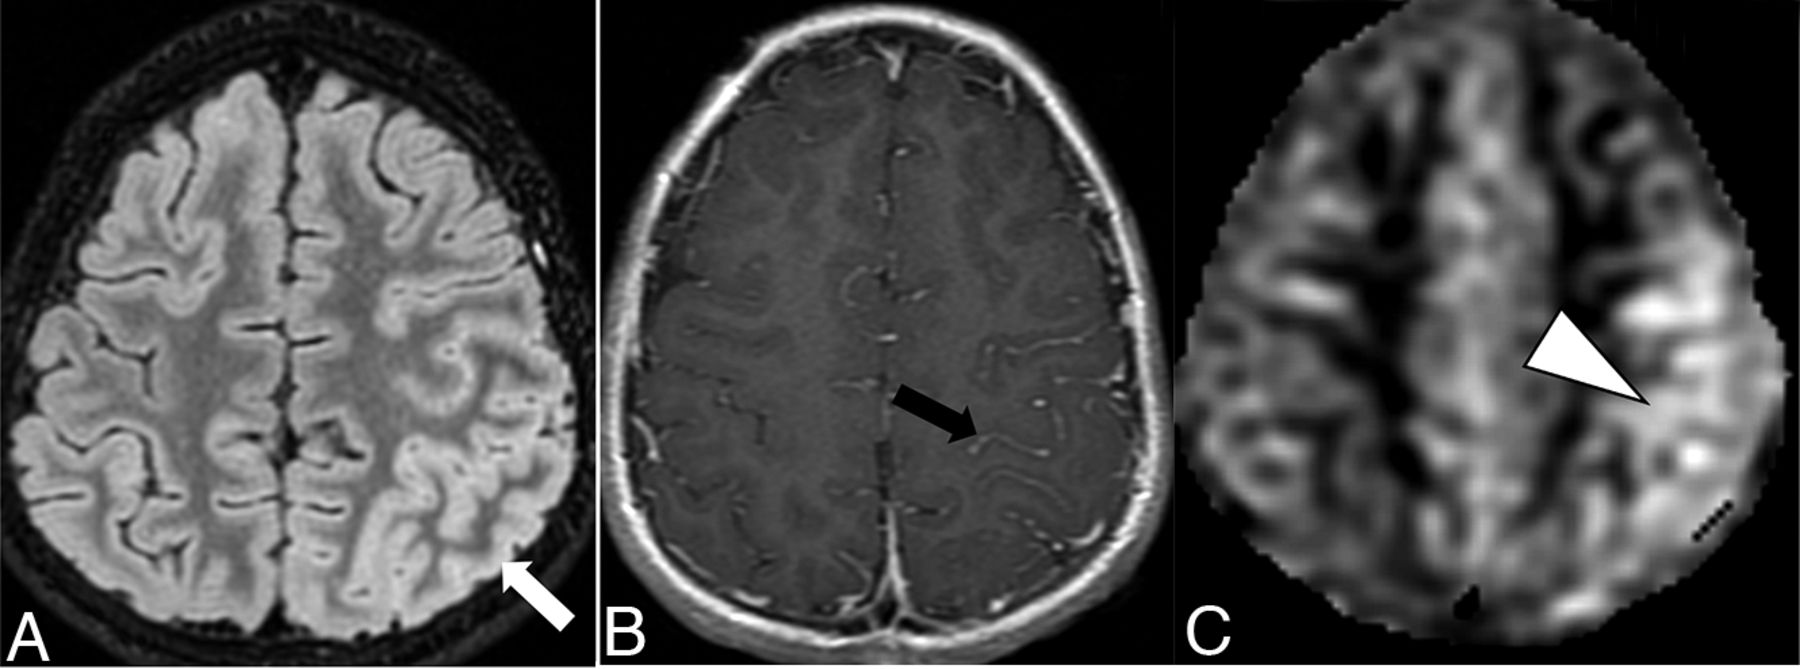

The overall imaging pattern was characterized as ADEM-like, optic neuritis (ON), myelitis (any cord signal abnormality), FLAIR-hyperintense lesions in anti-MOG-associated encephalitis with seizures (FLAMES), or any combination of the above. ADEM-like pattern was defined as multifocal supratentorial or infratentorial white or gray matter T2/T2-FLAIR hyperintense lesions with or without enhancement (Fig 1). When FLAMES occurred in combination with other patterns (ADEM-like, ON, or myelitis), the overall pattern was assigned as FLAMES (Fig 2).

Ten-year-old boy with rapid-onset altered mental status and seizures. A, Cortical FLAIR hyperintensity (white arrow) involving the left parietal lobe. B, Associated leptomeningeal enhancement (black arrow). C, Concurrently acquired arterial spine labeling image demonstrates hyperperfusion of the left parietal cortex (white arrowhead), reflective of associated seizure activity.